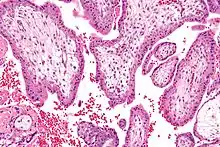

Biópsia das vilosidades coriónicas

A biópsia das vilosidades coriónicas é um exame de diagnóstico que consiste na recolha de uma amostra das vilosidades coriónicas do útero, as membranas embriónicas exteriores. Embora semelhante à amniocentese, este exame pode ser realizado bastante mais cedo, geralmente entre as oito e doze semanas de gestação, o que em caso de resultados desfavoráveis permite optar pela interrupção da gravidez numa fase precoce. Por ser realizado mais cedo, apresenta um risco de aborto espontâneo significativamente superior ao da amniocentese (1-2%).[1][72]